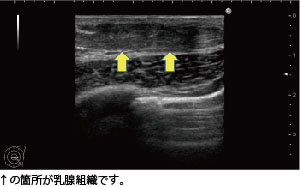

女性化乳房の治療前には、必ずエコー検査を実施

当院では女性化乳房の治療を行う際、必ず乳腺専用のエコーで検査を行って、原因を見極めたうえで治療を進めます。

このモニターゲストに関しては、皮下脂肪はそれほど多くなかったものの、乳腺の発達が認められましたので真性女性化乳房と診断しました。

当院では女性化乳房の治療を行う際、必ず乳腺専用のエコーで検査を行って、原因を見極めたうえで治療を進めます。

このモニターゲストに関しては、皮下脂肪はそれほど多くなかったものの、乳腺の発達が認められましたので真性女性化乳房と診断しました。